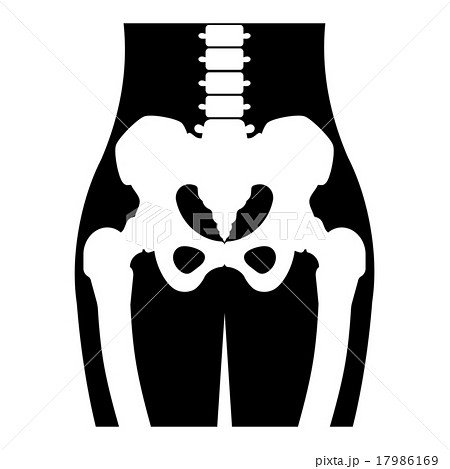

下半身 骨 イラスト

骨下半身のイラスト 医療のイラスト 写真 動画 素材販売サイトのメディック Medick

骨下半身のイラスト 医療のイラスト 写真 動画 素材販売サイトのメディック Medick

下半身の骨 イラストキット

下半身 骨イラスト 無料イラストなら イラストac

下半身の骨 イラストキット

下半身 骨イラスト 無料イラストなら イラストac

骨下半身のイラスト 医療のイラスト 写真 動画 素材販売サイトのメディック Medick